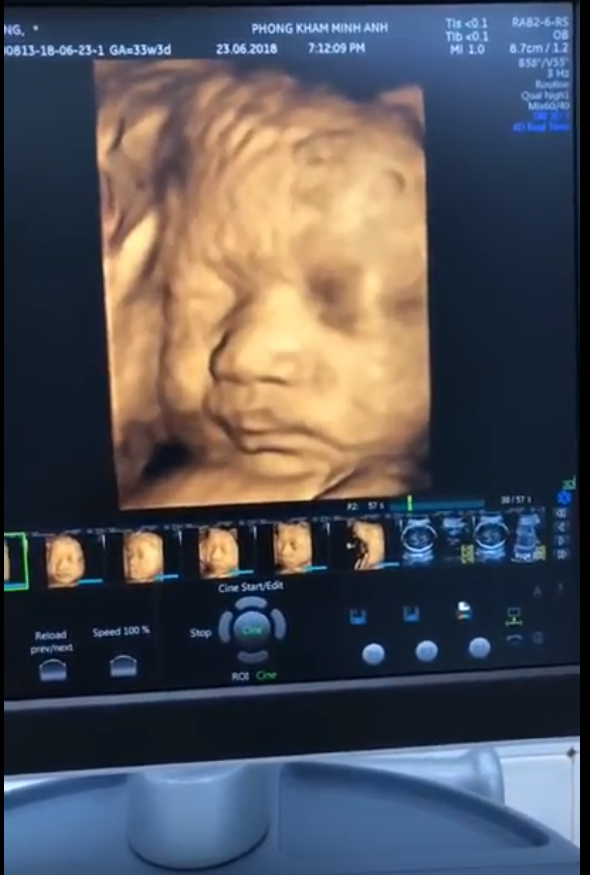

Bạn đã bao giờ thấy em bé mở mắt ngay khi còn trong bụng mẹ chưa???❤️❤️❤️???

Th7 05, 2018Các mẹ cho ý kiến gì về ảnh của con?

Hình ảnh siêu âm 4D của sản phụ Lệ Quyên, 1 trong những sản phụ đã đến khám và nhận quà tại phòng khám Sản phụ khoa Minh Anh Share this...